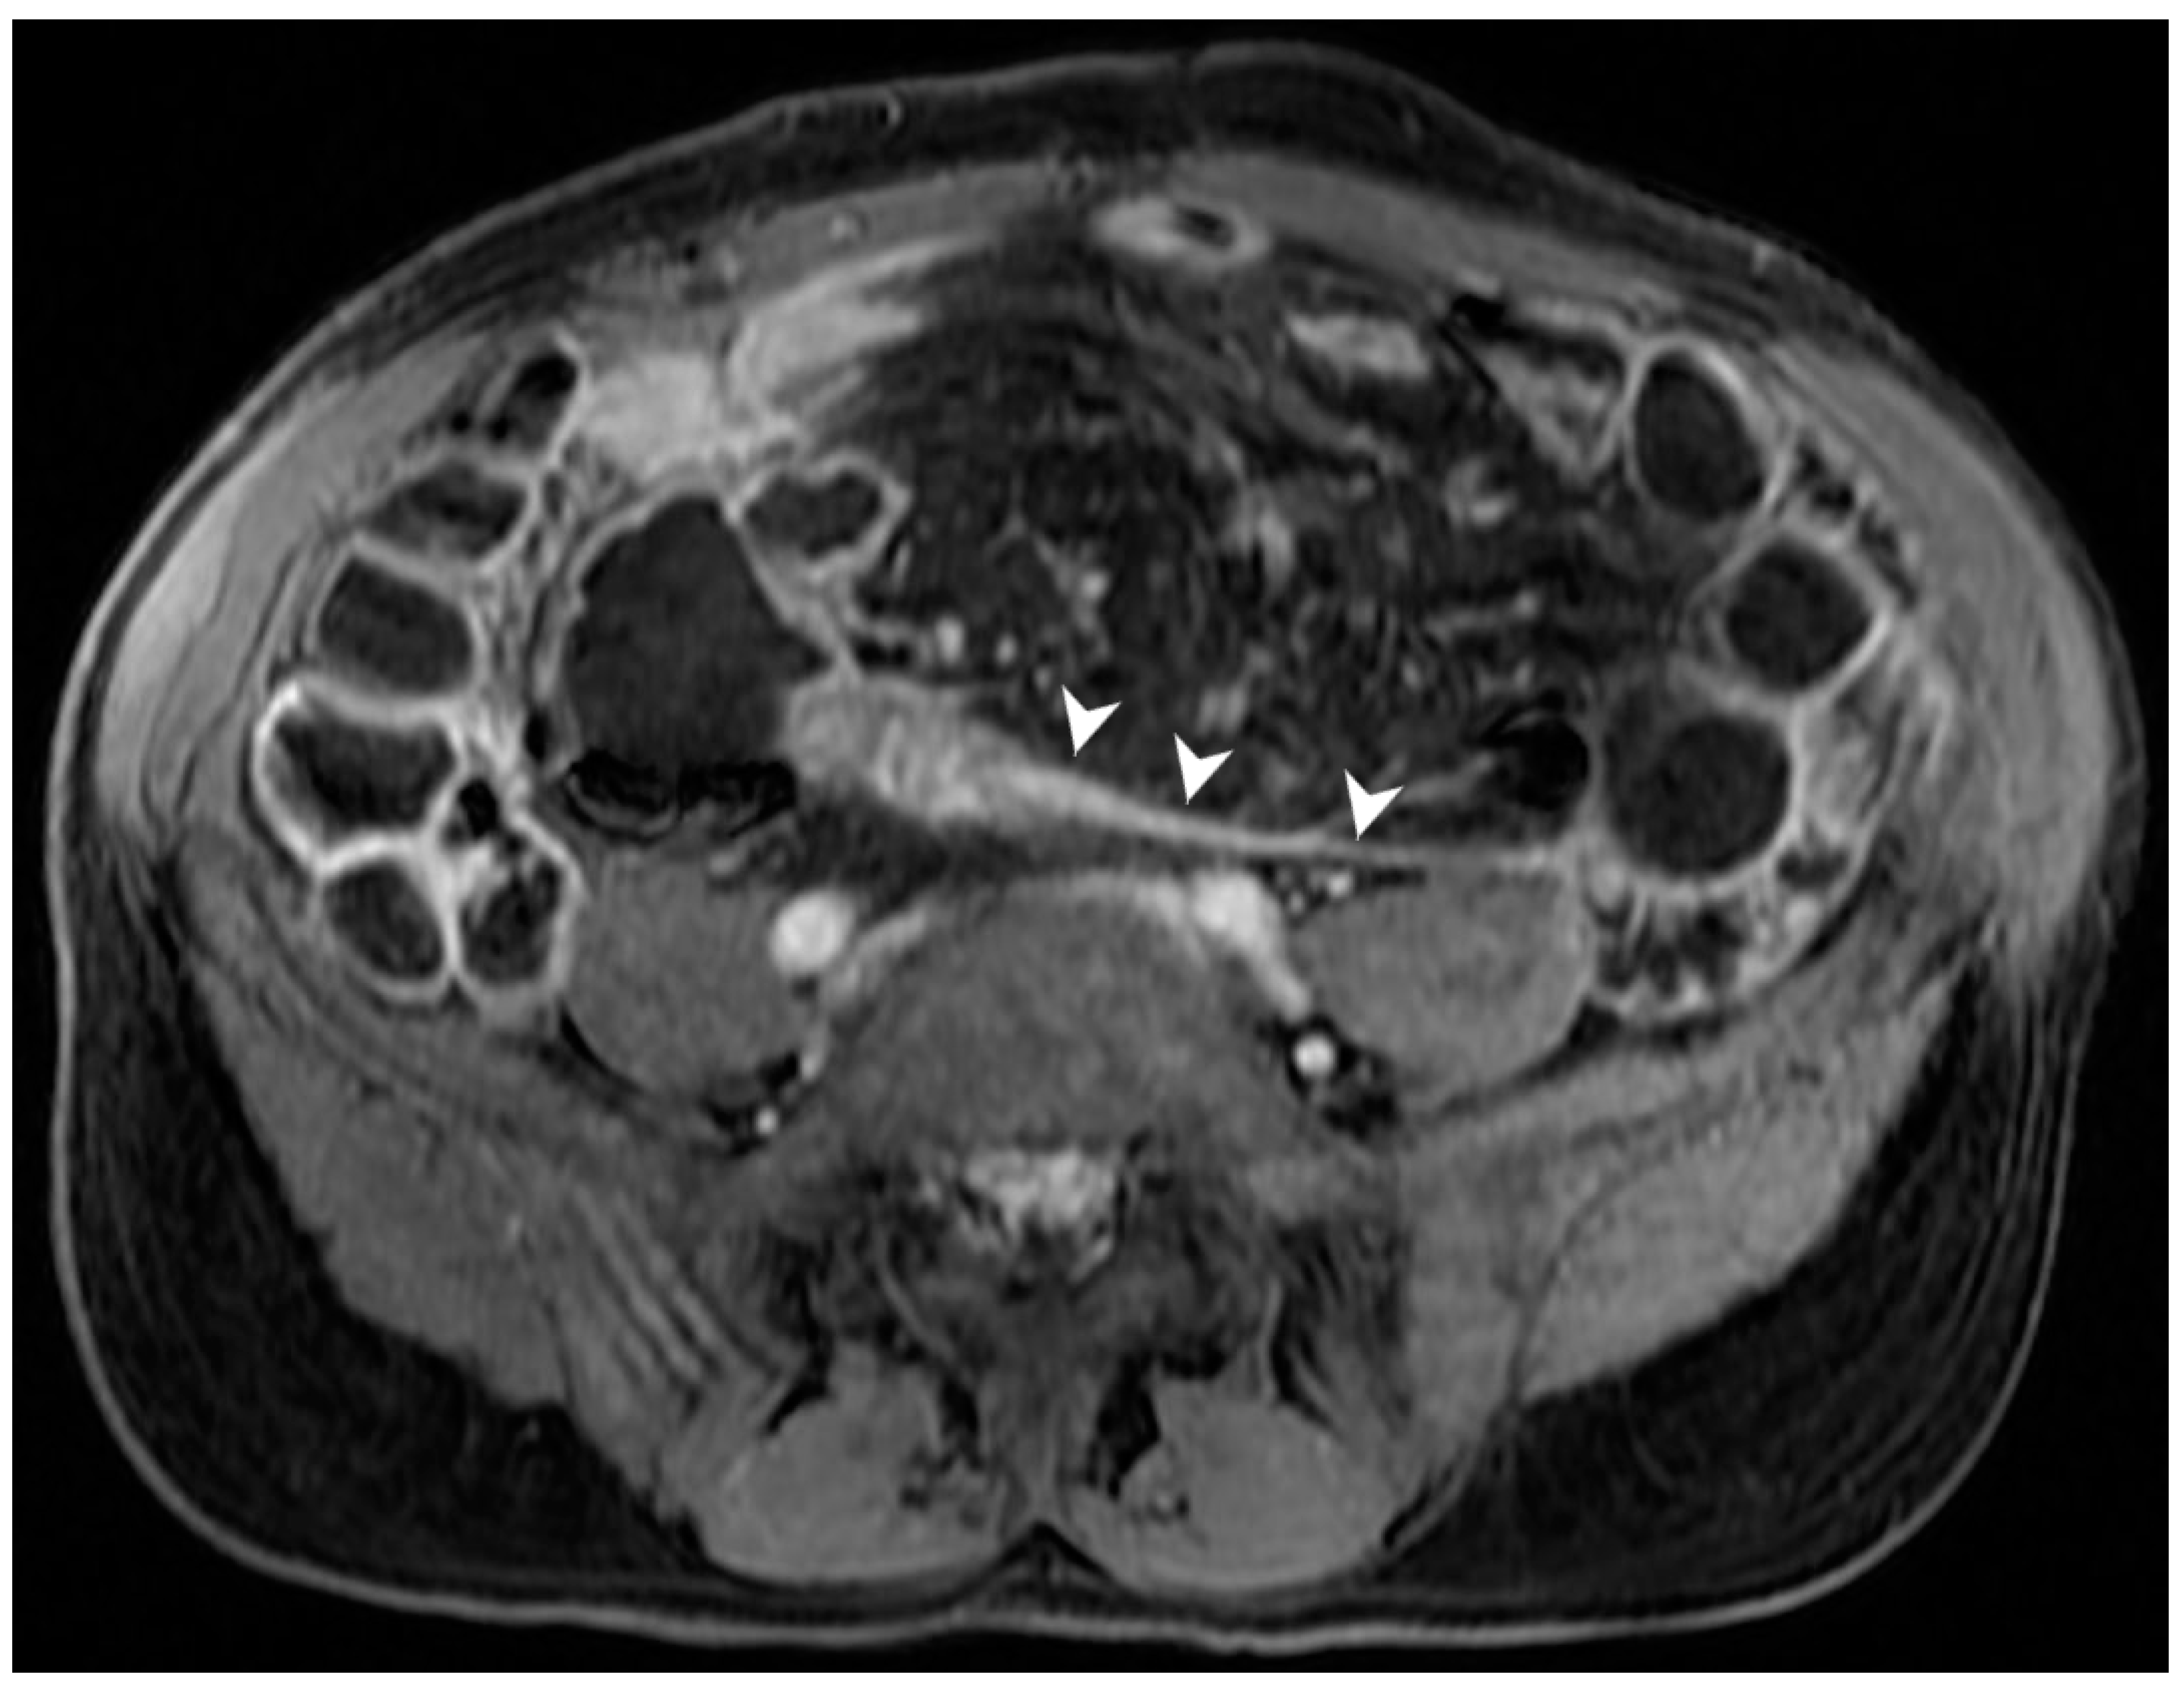

5.3. Fistulising/Perforating Subtype